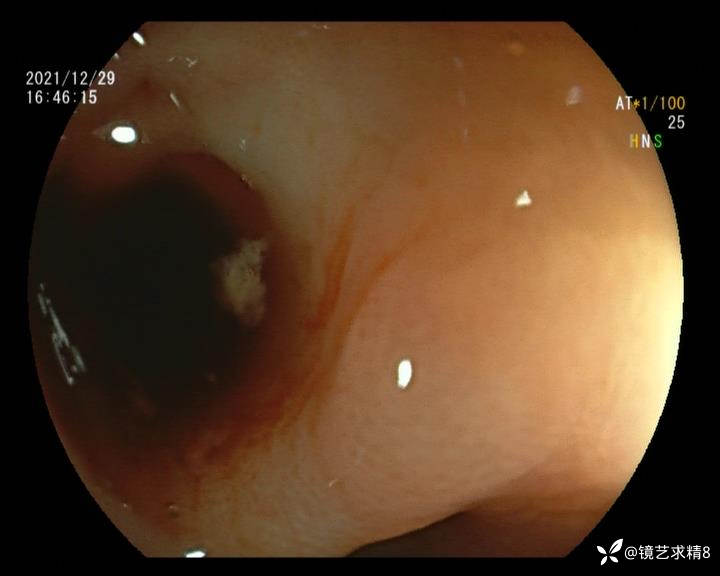

患者以消化道出血入院,胃镜未见异常,肠镜进入乙状结肠就看到很多憩室,同时还看到肠腔用清肠药后移动下来1枚尖锐的枣核,这么多憩室,这个枣核扎入憩室的机会非常大,推测应该是掉入一坑🕳就算出来还会有很多坑🕳🕳🕳等着,掉入憩室内很容易刺破血管,这可能就是消化道出血的原因,继续前进可以看到有一些憩室内翻,还有一些息肉,问题来了,那么多憩室,犯罪分子是抓住了,它在那些憩室内作过案?到达回盲部后挨个冲洗,但憩室大小又不足以把镜头进入憩室内观察,针对有血块的憩室冲洗后可疑出血的以夹子闭合或套扎,取出枣核,如果有锥形透明帽可能钻入憩室精准电凝效果更好,若内镜下操作失败介入治疗成功率更高,经内镜下治疗后观察未再出血出院。